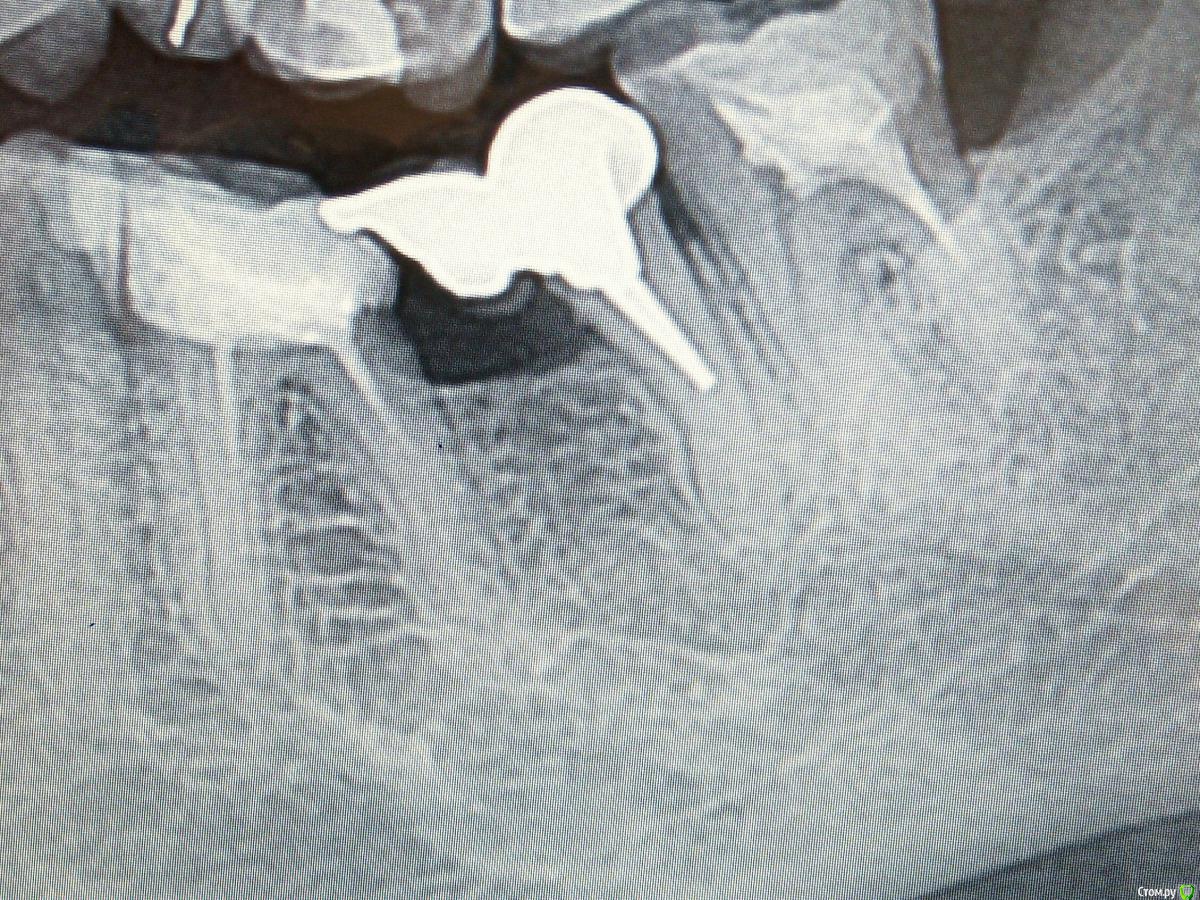

igorstom Опубликовано 24 ноября, 2019 Автор Поделиться Опубликовано 24 ноября, 2019 Вот пример работы через некоторое время с гемисекцией. Можно конечно задать резонный вопрос: почему каналы не пролечены.... Объясняю. Работа делалась абсолютно бесплатно. Ну человек такой мне попался - блатной, родственница начальников. А как известно бесплатный сыр только на сыр-заводе. Поэтому с каналами в данном случае просто не стал заморачиваться. Ведь по "леченым" каналам видно, что пациентка лечилась всегда на халяву с вытекающими отсюда последствиями для своих зубов. А перелечка чужого эндо это всегда сильный геморрой. Работа проводилась в Госке. 2 Ссылка на комментарий

сирена Опубликовано 24 ноября, 2019 Поделиться Опубликовано 24 ноября, 2019 Вот пример работы через некоторое время с гемисекцией. Можно конечно задать резонный вопрос: почему каналы не пролечены.... Объясняю. Работа делалась абсолютно бесплатно. Ну человек такой мне попался - блатной, родственница начальников. А как известно бесплатный сыр только на сыр-заводе. Поэтому с каналами в данном случае просто не стал заморачиваться. Ведь по "леченым" каналам видно, что пациентка лечилась всегда на халяву с вытекающими отсюда последствиями для своих зубов. А перелечка чужого эндо это всегда сильный геморрой. Работа проводилась в Госке.Резорциненные зубы?Нет совсем периапикальных изменений. Ссылка на комментарий